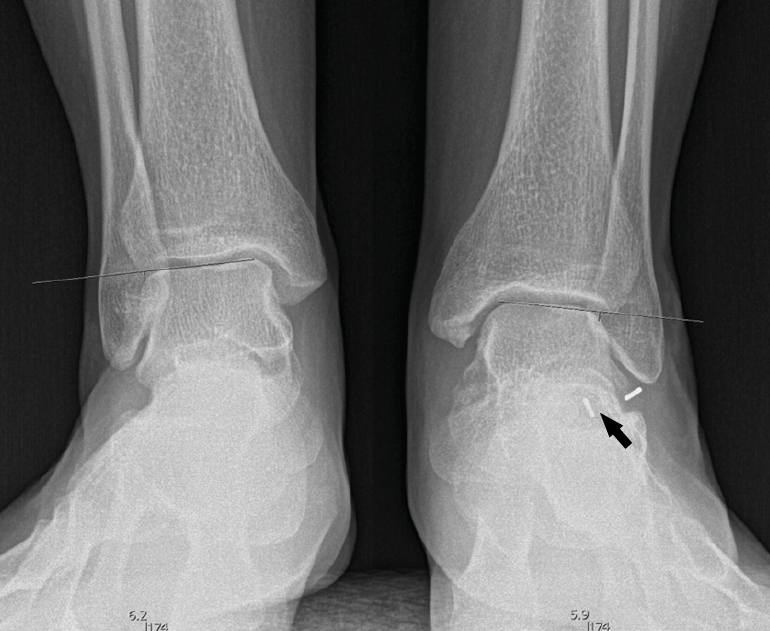

Segundo caso (Figura 7)

Se trata de una paciente mujer de 18 años de edad, higienista dental, sin antecedentes patológicos de interés, que presenta pies planos valgos bilaterales dolorosos, el derecho de 23° y el izquierdo de 21° de valgo, por sinostosis calcaneoastragalina media en ambos pies. En ella observamos básicamente una clínica de dolor en el seno del tarso, con déficit de movilidad de la articulación subtalar en ambos pies. Se realiza estudio mediante radiografías de los pies y los tobillos en carga y TAC de ambos pies (afectación bilateral). Radiológicamente, las articulaciones tibioperoneoastragalina y subtalar están preservadas. Se diagnostica de coalición tarsal de tipo 4 de la clasificación de Rozansky(26). El balance articular es de: flexión = 45°; extensión = 20°; inversión = 0°; eversión = 0°. La escala de la AOFAS para el tobillo derecho presentaba una puntuación de 62 (20-37-5). Los ángulos radiológicos iniciales son: Moreau-Costa-Bartani interno = 141°; declinación talar = 18,4°; Meary = 6,3°; Kite = 25,6°; taloescafoideo = 48,3°.

Figura 7. Radiografía del segundo caso: sinostosis talocalcánea media en ambos pies.